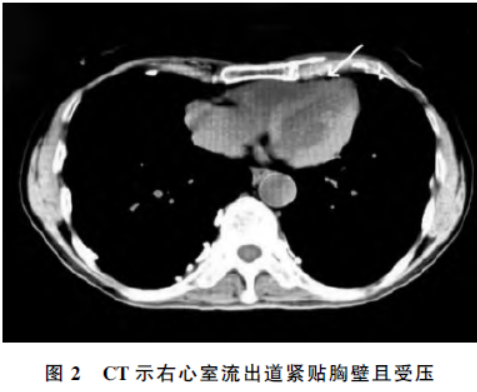

查看患者胸部CT,见右心室流出道紧贴胸壁并受压,该处心前间隙消失,测量胸廓前后径/胸廓左右径为0.34(图2),结合患者临床症状,确诊为直背综合征。

但诊断该病的金标准为CT和X线,当胸廓前后径与横径之比<0.4,或测量T8距T4与T12椎体前缘连线的垂直距离小于1.2 cm 时可诊断为直背综合征。该病较罕见,但诊断并不难,提高对该病认知,从而避免漏诊、误诊,有效的体格检查及典型的影像学检查可帮助诊断。